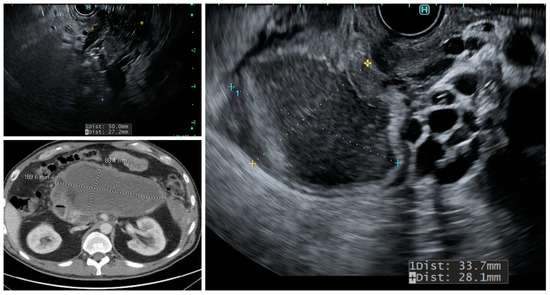

MCN, SCA, and SPN are solitary cysts. MCN and SCA lack communication with the main pancreatic duct and do not show pancreatic duct dilation on imaging. IPMN, by definition, demonstrate communication with the pancreatic duct, have the dilation of the duct, and are commonly multiple. IPMNs are more common in the head and neck region but can be found in other locations (Figure 2). They can be multifocal and should be considered along with pseudocysts when multiple cysts occur in the pancreas. MCNs are exclusively seen in the body or tail of the pancreas (Figure 3). While SCA can occur in the head, most SCA are located in the body or tail (~70–75%). There is no specific location of SPN (Table 1).

Figure 2.

CT scan and endoscopic ultrasound demonstrating a side-branch IPMN involving the head of pancreas (HOP) with a calcified mural nodule.

IPMN: The distribution of cysts in relation to the main pancreatic duct determines the malignant behavior of IPMN. Consequently, IPMN are classified as the main-duct IPMN (MD-IPMN) when MPD is dilated due to the direct involvement for more than 5 mm without a visible cyst, branch-duct IPMN (BD-IPMN), when there is a cyst, >5 mm without dilated MPD, and mixed-type when there is one or more PC > 5 mm along with the involvement of MPD. MD-IPMN and mixed-type IPMN have a higher risk of harboring invasive adenocarcinoma (approximately 45%) and high-grade dysplasia (approximately 60%), while BD-IPMN are at lower risk (16–20%) [11]. Moreover, the rate of cyst growth on follow-up can predict the risk of malignant behavior in BD-IPMN [12]. MPD dilation >10 mm in MD-IPMN, with a cyst diameter >40 mm in BD-IPMN, and the presence of a large mural nodule on EUS favor malignancy (Figure 2) [13]. Pergolini et al. followed up patients with BD-IPMN for over 10 years and found that the risk of malignancy was significant (approximately 8%) for cysts > 1.5 cm even after the five years of suggested surveillance period [14].

CT and MRI have a comparable sensitivity at differentiating malignant from benign PC, and both have equivalent accuracy at making a specific diagnosis (50–60%); however, the rate of misdiagnosis is remarkable with either imaging modality (>50%) [25,26,27]. MRI is considered better than CT at evaluating cyst morphology. Consequently, the major advantages of MRI and MRCP over CT scans are characterizing the aggressiveness of small cysts and detecting high-risk morphologic features, such as the mural nodule, septal thickening, and cyst communication with MPD (Figure 2).